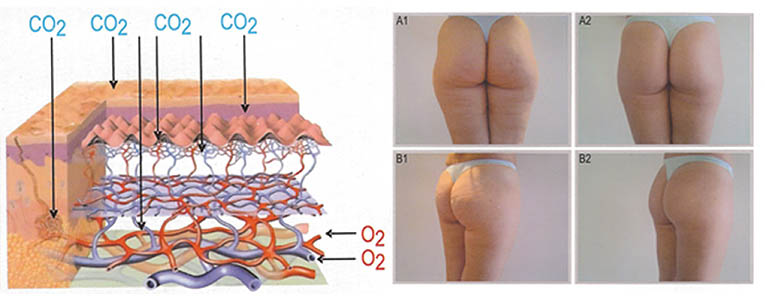

- Improves blood supply to mucosa and deeper tissues

The apparatus therapeutic effect is based on thermal effects enabling focused ultrasound waves to precisely target tissue and the depth NOT impairing any structures through which they travel. Transformation of HIFU waves energies into thermal energies achieves therapeutic effects which are exclusively NON-ABLATIVE and BIOSTIMULATIVE enabling the treatment to stimulateneosynthesis of collagen and its regeneration and reorganisation. It also encourages neovascularization of the treated area.

In recent years HIFU technology has been successfully applied in treatments of vaginal relaxation (VRS) and stress incontinence (SUI). Precise application of HIFU waves to vaginal walls at a depth of 3 to 4.5mm warms submucosa and mucous membrane to 65⁰C. This method practically instigates connective tissue of mucous membrane to regenerate. The treatment results in higher numbers of stronger, remodeled and narrowed collagen fibers which permeate and provide strength of vaginal walls. In addition, biostimulative effects of HIFU wave initiated regenerative processes have positive impacts on the elastic fibers of mucosa and pelvic muscles. Final results of the treatment are reflected by a narrowed vaginal canal with stronger, more resistant and healthier walls. All these effects are beneficial in the treatment of SUI hence why HIFU is also applied in treatments of first and second degree SUI whilst third degree SUI requires surgery. HIFU application in treatment of first and second degree SUI can significantly delay the development of third degree SUI and therefore delay or completely eliminate the need for surgical treatment.